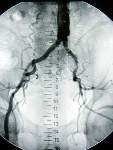

Při vyšetření nemocného se diagnosa stanovuje na základě všech dostupných anamnestických údajů a ze základního vyšetření pohledem a pohmatem. Při odůvodněném podezření na tuto chorobu se provádí nejprve vyšetření tepen ultrazvukem. Toto většinou stačí k vytvoření dobrého diagnostického základu k započetí therapie. U nemocných, kteří nemají noční bolesti a klaudikační interval je delší než 200 metrů, se má zahájit konservativní léčba. Tato spočívá v úpravě životosprávy, v ukončení kouření, v aplikaci léků a vhodném svalovém cvičení. Kontrastní vyšetření tepen rentgenem t.z. angiografie se provádí většinou až v případě, kdy se plánuje operační řešení uzávěrové choroby. To připadá v úvahu u nemocných s krátkým klaudikačním intervalem, nočními bolestmi nebo počínající periferní odúmrtí.

Na základě rtg obrazu tepen lze naplánovat rekonstrukční operaci. Principem těchto operací je v menším procentu případů přímý zákrok na tepně v místě zúžení či uzávěru, kdy se tepna otevře v potřebném rozsahu a uzávěr se odstraní za kontroly zraku. Druhý, více užívaný způsob rekonstrukce, je tzv. by pass, tedy vytvoření náhradního řečiště pomocí vlastní odebrané žíly nebo pomocí umělé protézy. Podmínkou všech rekonstrukčních výkonů je dobrý výtokový trakt, což znamená, že tepny, kam krev přivádíme, jsou dostatečně průchodné, aby se zajistil potřebný proud v novém řečišti. Zejména umělé protézy jsou velmi náchylné k uzávěru při průtoku pod 100-120 ml/min.

Mnohé případy klaudikací dolních končetin mají příčinu ve vysokém uzávěru tepen v pánvi. Proto je třeba některé operace provádět za otevření dutiny břišní. Z toho vyplývá, že ne všechny uzávěry jsou spolehlivě rekonstruovatelné a že většina cévních výkonů jsou komplikované operace, náročné na čas i operační zátěž nemocného. Operace by byla takovou zátěží, že by nemocný mohl zemřít na srdeční či plicní pooperační komplikace. Každá cévní operace je riziková z důvodu možné infekce. Zatímco infekční komplikace operací v oblasti dutiny břišní jsou častější, nemusí mnohdy nikterak nepříznivě ovlivnit dobrý výsledek operace. Infekce protézy nebo tkání v okolí cévních švů vedou prakticky vždy ke kompletnímu neúspěchu cévní rekonstrukce.